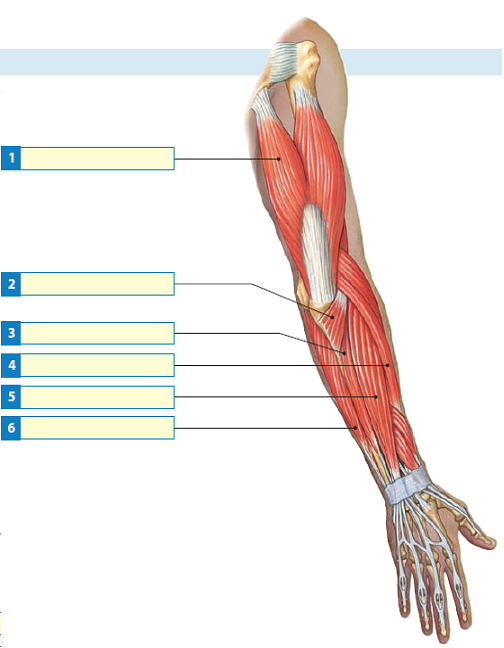

Анатомия мышцы Palmaris Longus